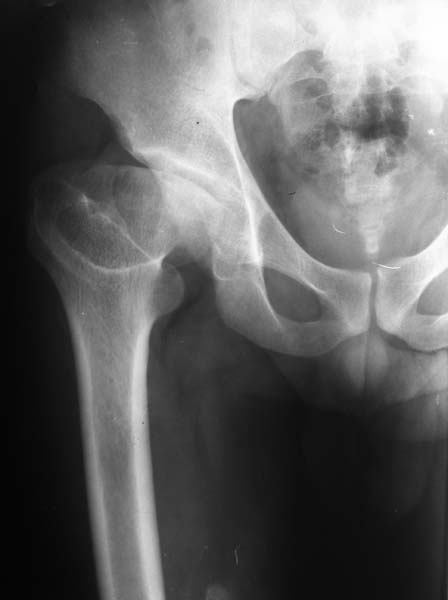

Больной, 24 года,

спортсмен - борец вольного стиля, рост 170см, вес 92кг. Со слов была травма в детстве, но

характер травмы описывает смутно и мед. документацию не предоставляет. Жалобы на

периодические боли в области т/б сустава, но больше смущает укорочение конечности и

хромота. Похоже на последствия остеохондропатии головки бедренной кости

(Легга-Кальве-Пертеса) или неправильно консолидированного перелома. Объем движений в

т/б суставе в пределах нормы, но по сравнению со здоровой ограничено: внутренняя ротация на

15гр., отведение до 25-30гр., наружняя ротация, сгибание, разгибание и приведение

одинаково. Укорочение конечности 4.5см. Отмечается незначительная гипотрофия мышц бедра

и голени: бедро в объеме меньше здорового на 5см, голень на 3см. Опыта ТЭТС при данной

патологии у нас нет. Хотим отправить пациента за пределы республики. Больной к оперативному

лечению морально и материально подготовлен)) При необходимости можно оформить квоту на

ТЭТС.